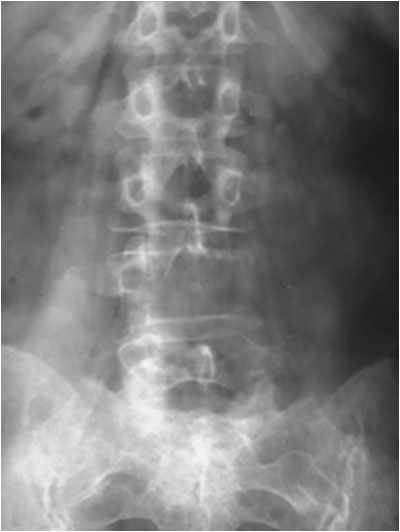

SIGNO DEL BORDE

Engrosamiento de la línea ileopectínea vista en la radiografía de pelvis, que corresponde a la afectación de este hueso en la enfermedad de Paget. Este signo, que corresponde a reacción osteoblástica en la zona, está presente en la mayoría de pacientes con enfermedad de Paget pélvica.